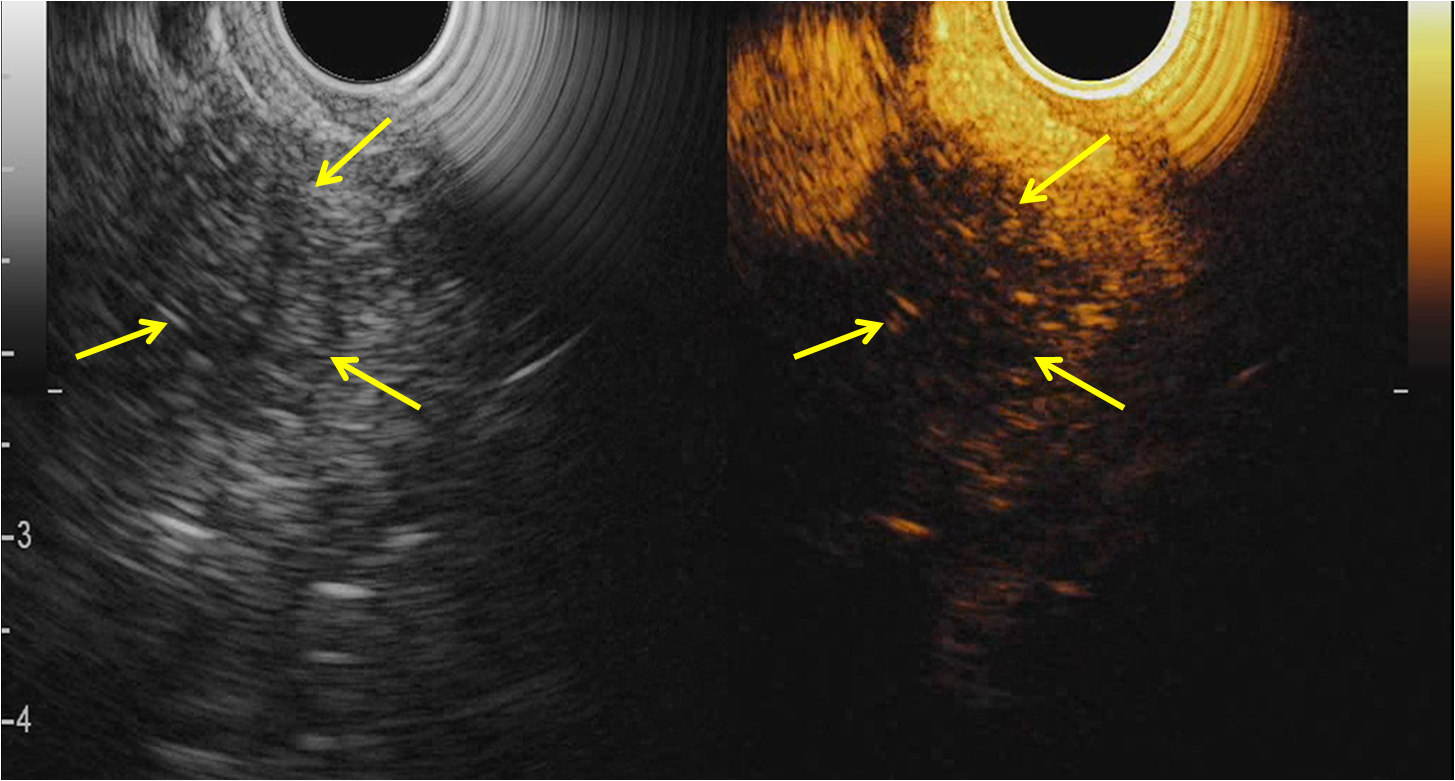

2. ЭУС - контрастное усиление новообразования поджелудочной железы: слабое накопление контраста | |